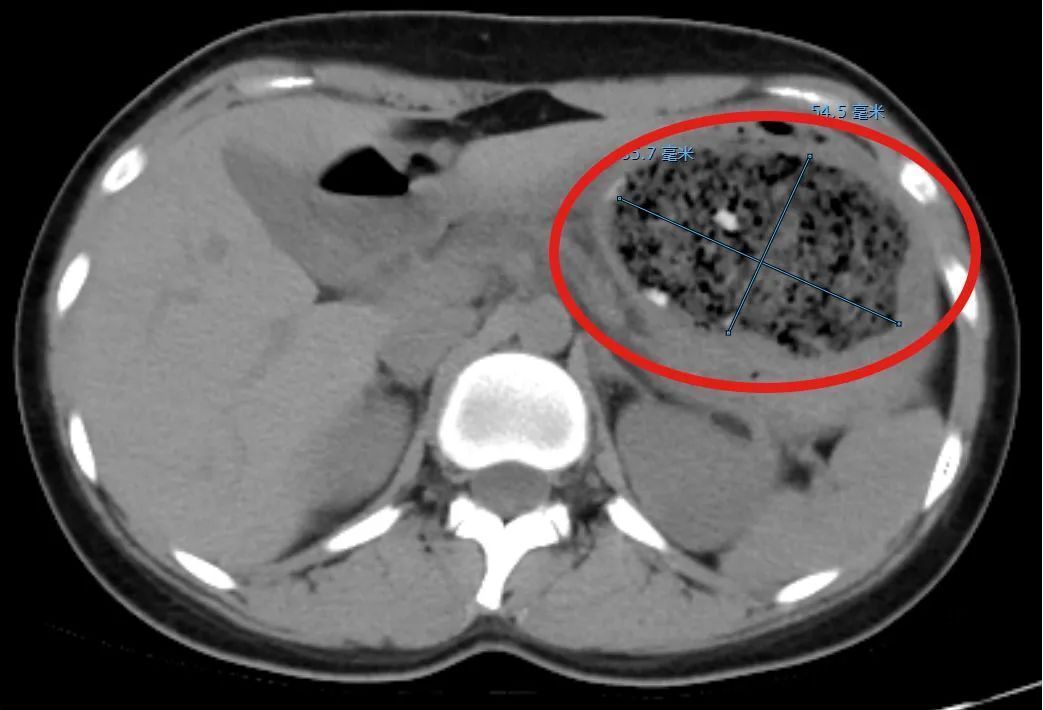

接诊的消化内科副主任杨晶简单问了病史后,给倩倩安排了腹部CT平扫检查,结果发现一个8.6cm×5.5cm左右的巨大异物把她的胃塞得满满当当。

在进一步胃镜检查后,杨晶发现,倩倩胃里面的结石体积庞大,几乎不留什么空隙,这使得常规的异物圈套器无法施展。